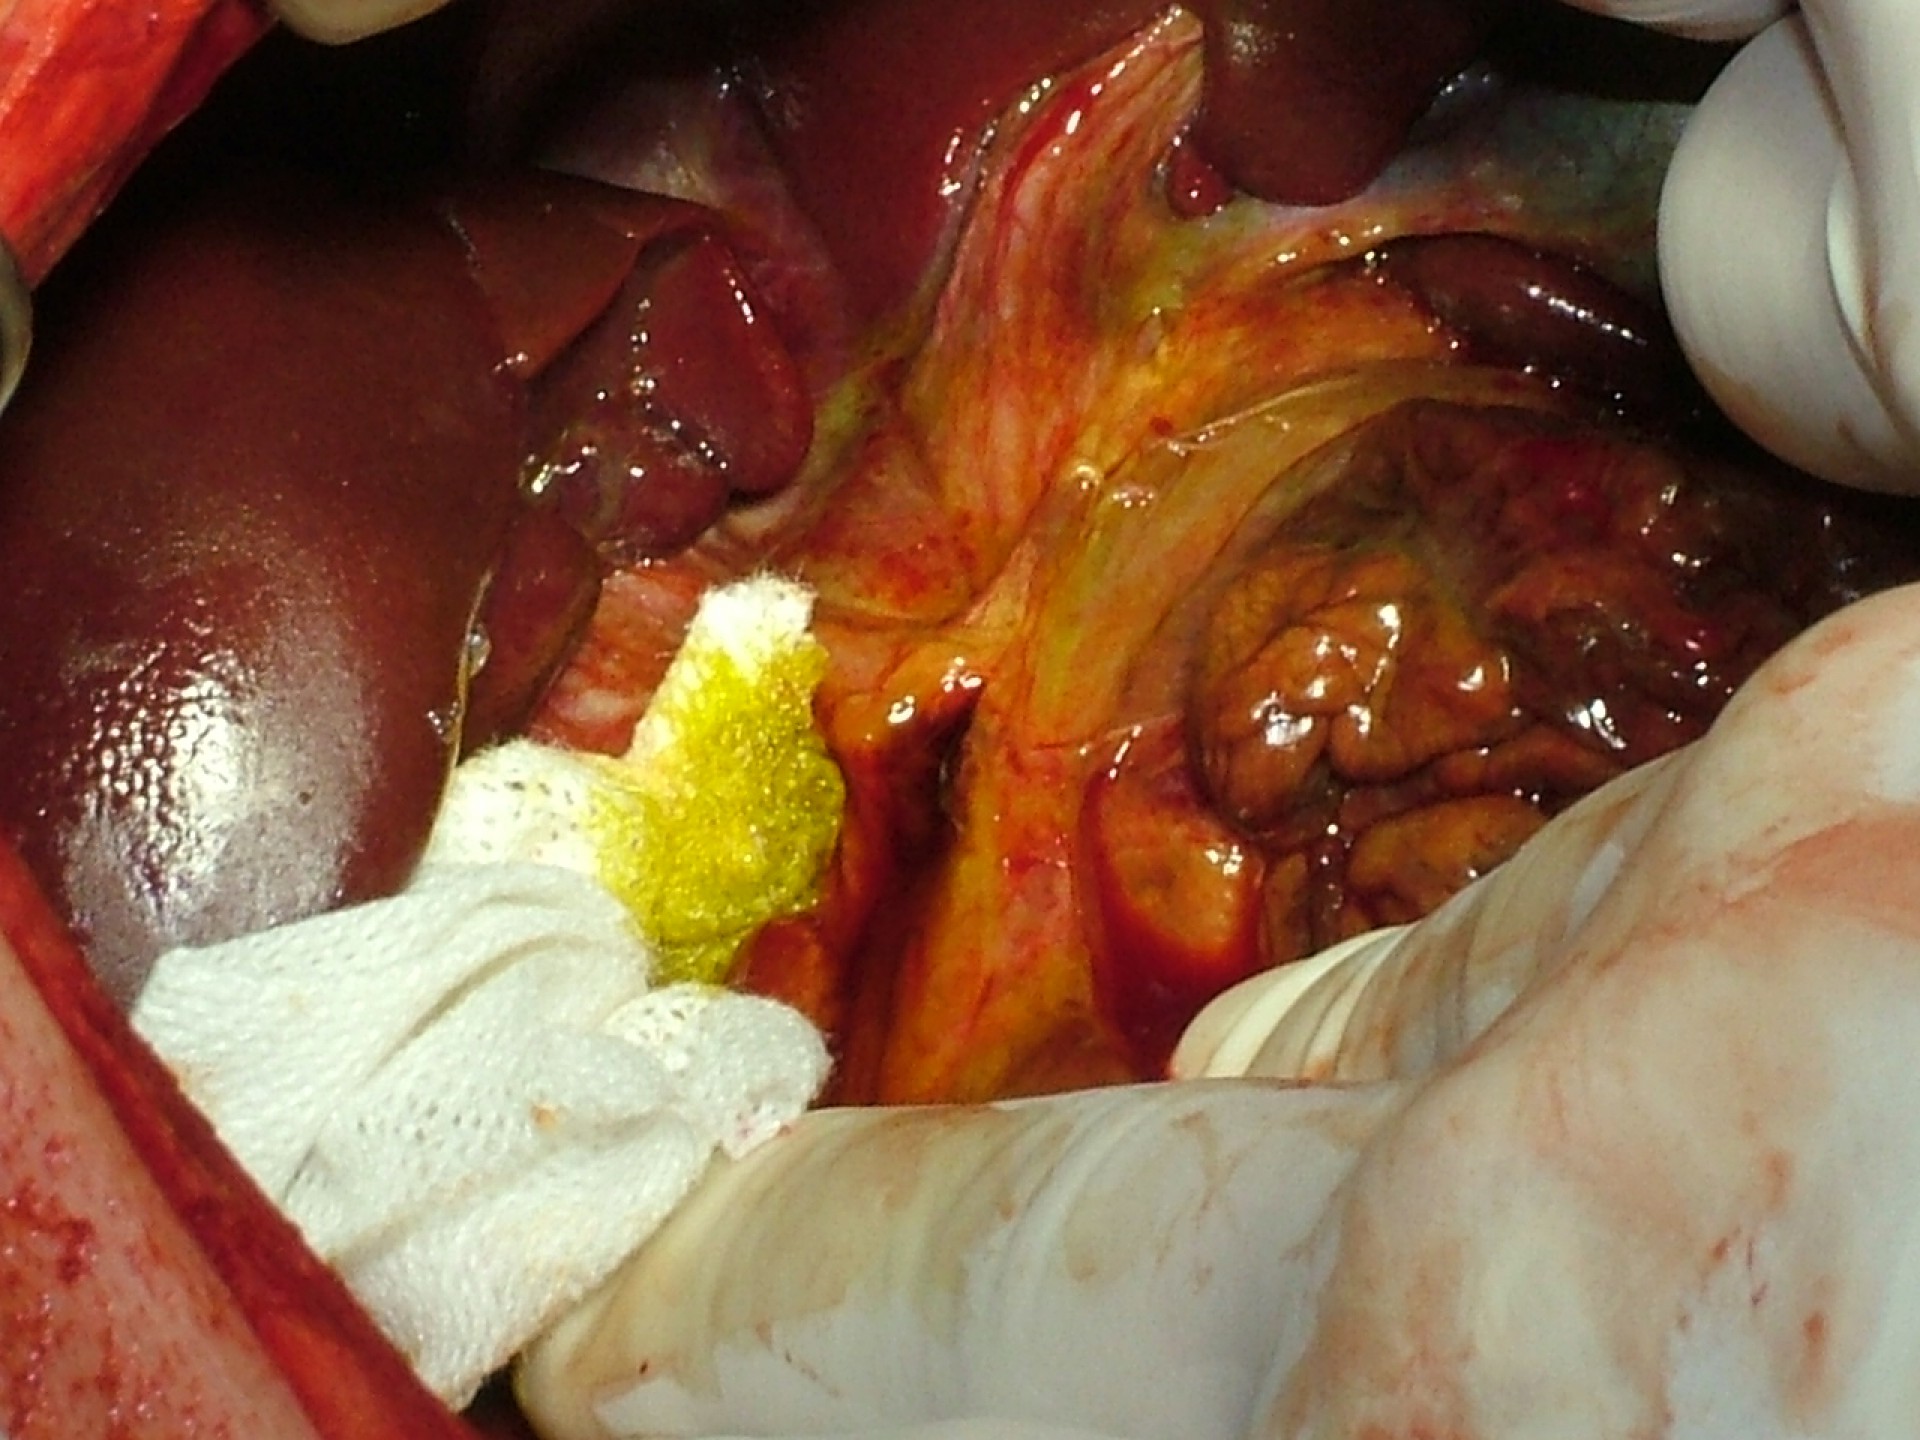

A feltárás során kb.: 2 liternyi mennyiségű szabad hasüregi tartalmat távolítottunk el. Miután a hasüreget vizsgálhatóvá tettük elképedve tapasztaltuk, hogy lépet, a beleket, a csepleszt - mindent a hasüregben- nagy mennyiségű sötétzöld epe borít. Annak az esélye, hogy ezt maradék nélkül eltávolítsuk minimális, így a további hashártyagyulladás nem előzhető meg.

De honnan került az epe a hasüregbe? A máj alapos vizsgálata során daganatra, traumára utaló jelet nem láttunk, így az epeutakat vettük szemügyre. Ép epehólyag mellett a közös epevezetőn egy kb.: 3 mm hosszú repedést találtunk, melyen keresztül az epehólyag megnyomásával epe ürült a hasüregbe. Hogy mi okozta a repedést? Soha nem derül ki…

De legalább megvan a forrás, így tudunk tenni ellene! Az epevezető sérülését elláttuk, a szakadást bevarrtuk. De mi van, ha a szakadás helyén a hashártya gyulladása miatt zsugorodás alakul ki és az epevezető elzáródik? Az epe ismét nem jut a bélbe, az epehólyagban felhalmozódik és annak gyulladását, repedését idézheti elő. A probléma pedig kezdődik megint…Meg kell oldanunk az epe bélbe történő szabad áramlását!

Cholecystojejunostomia. Szép szó! Már rég vágytam rá, hogy egy ilyen műtétet csinálhassak! Nem mindennapos dolog, amikor az epehólyagot(cholecysta) a vékonybél egy részéhez( jejunum) szájaztatjuk(stoma), így biztosítva az epe szabad áramlását a bélbe. Igazi kihívás!